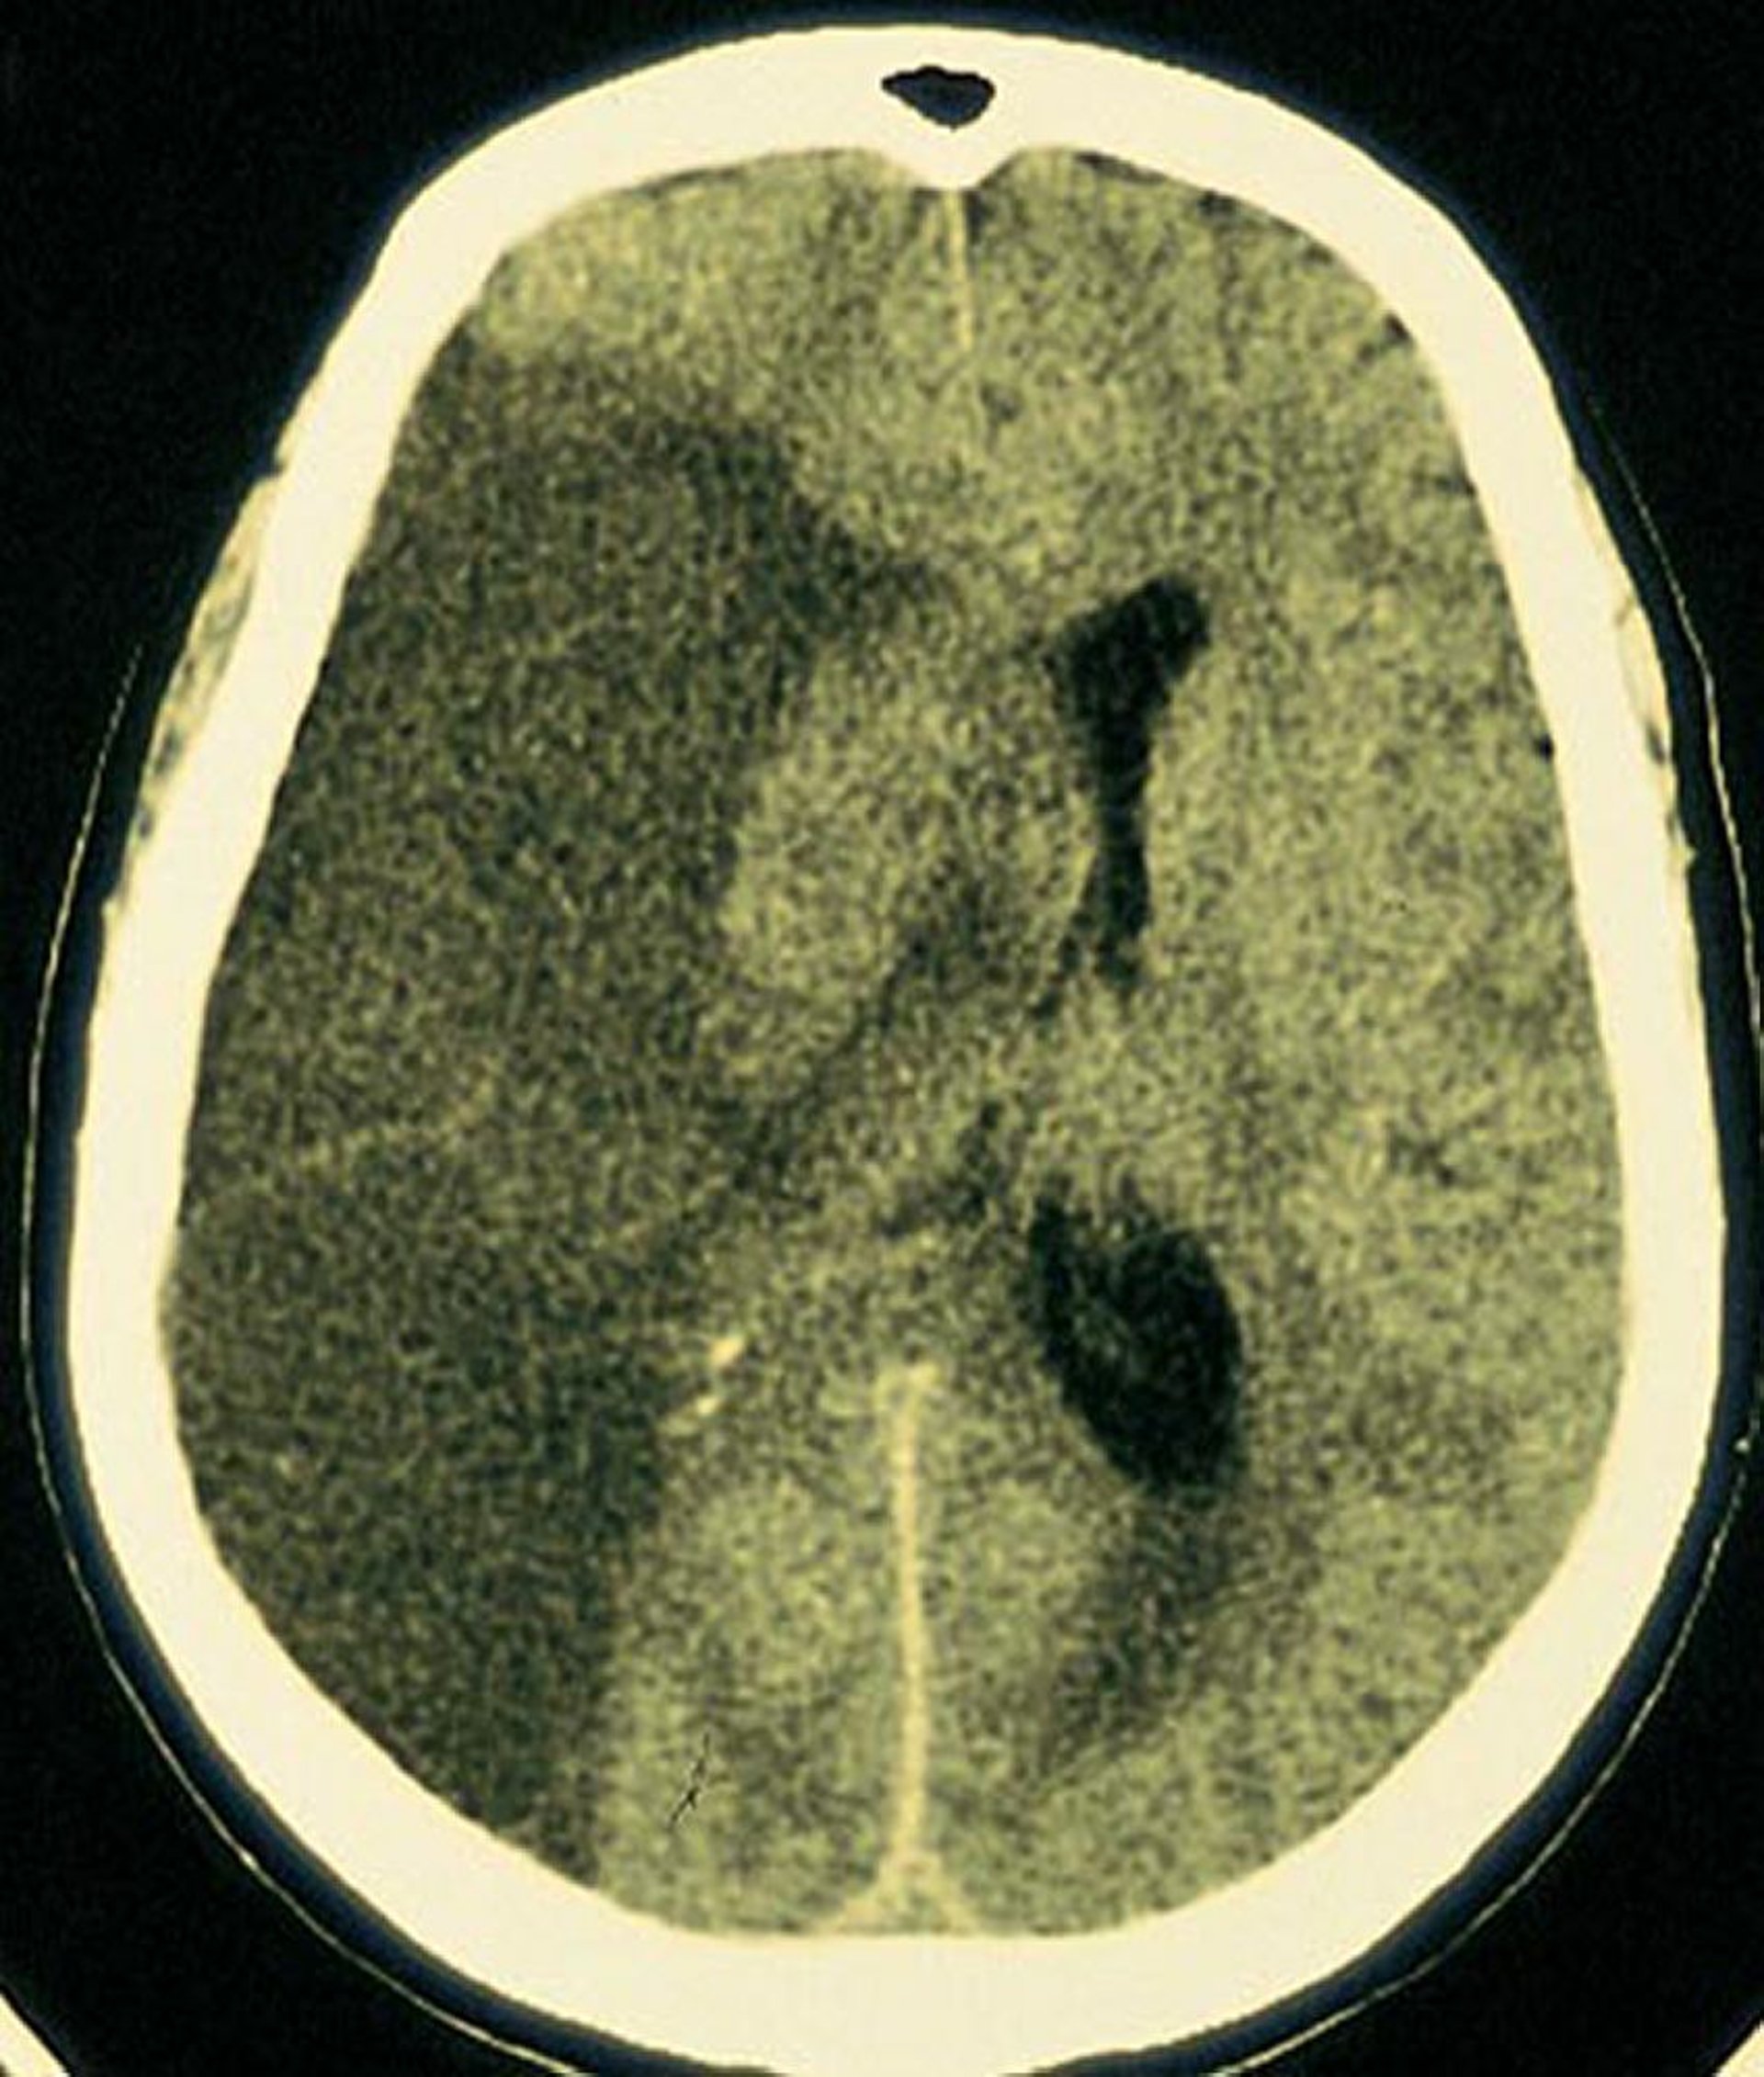

Middle Cerebral Artery Infarct

A large lucent infarction is seen in the area of brain supplied by the right middle cerebral artery.

By permission of the publisher. From Furie K, et al: Cerebrovascular disease. In Atlas of Clinical Neurology. Edited by RN Rosenberg. Philadelphia, Current Medicine, 2002.